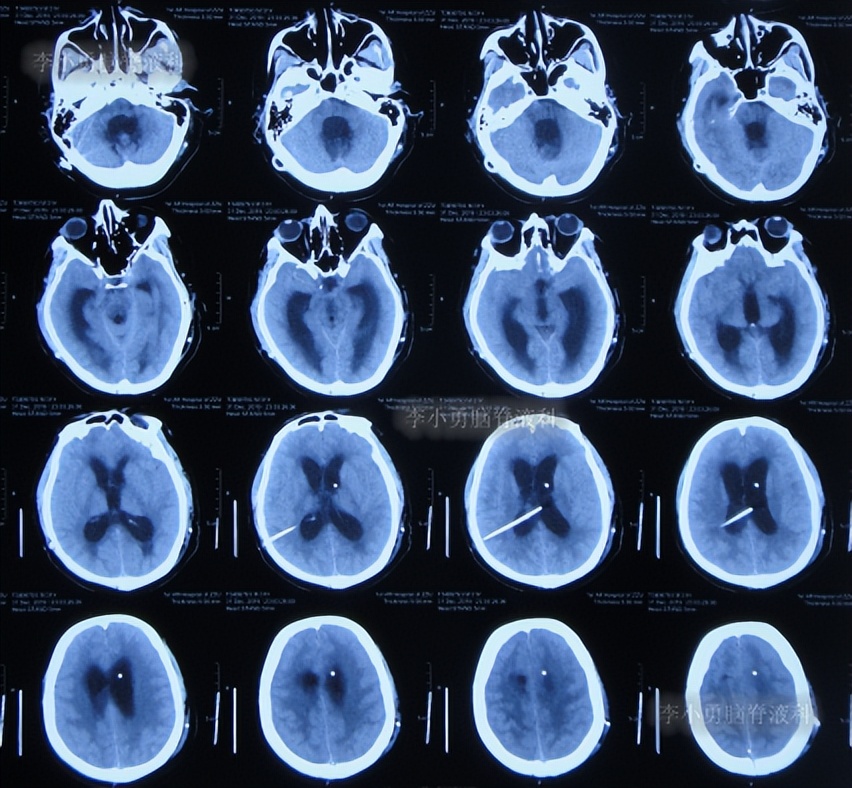

出院后1年半期间,仍时有视物重影的症状,并未给予处理,但到2019年9月27日(脑室腹腔分流术后1年零6个半月),出现头晕,恶心呕吐,视物重影加重,5天后因症状无缓解,就诊于当地的河南省临颍县某医院,查脑CT示脑积水(图-1);给予腰穿检查示颅内压力高220mmH2O。

图-1:2019年10月3日头颅CT

脑室分流管探查调整术后5天即2019年10月10日,患者症状好转,查头颅CT示脑室缩小(图-3)。

图-3:2019年10月10日头颅CT

第3次出院后24天即2019年11月10日,因视物又出现模糊,在当地医院查头颅CT示脑室又有扩张(图-4),给予手术的医生建议继续观察。

图-4:2019年11月10日头颅CT